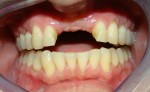

A Case with a Fractured Central Incisor

• They look and feel like solid natural teeth

• They maintain bone volume due to the physical demands placed on the bone.  No hollowing out of the gum as seen under and around dentures and bridges.